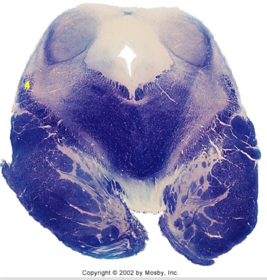

| Nucleus gracilis | |

| Nucleus cuneatus | |

| Fasciculus gracilis | |

| Fasciculus cuneatus | |

| Internal acruate fibers | |

| Lateral (external/accessory) cuneate nucleus | |

| Medullary pyramids | |

| Hypoglossal nucleus | |

| Hypoglossal nerve | |

| Dorsal motor nucleus of X | |

| Nucleus ambiguus | |

| Solitary tract | |

| Solitary nucleus | |

| ALS | |

| Medial lemniscus | |

| Medial longitudinal fasciculus | |

| Spinal tract of V | |

| Spinal nucleus of V | |

| Lateral (external, accessory) cuneate nucleus | |